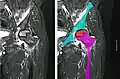

In the early stages, bone scintigraphy and MRI are the preferred diagnostic tools.[18][19]

X-ray images of avascular necrosis in the early stages usually appear normal. In later stages it appears relatively more radio-opaque due to the nearby living bone becoming resorbed secondary to reactive hyperemia.[2] The necrotic bone itself does not show increased radiographic opacity, as dead bone cannot undergo bone resorption which is carried out by living osteoclasts.[2] Late radiographic signs also include a radiolucency area following the collapse of subchondral bone (crescent sign) and ringed regions of radiodensity resulting from saponification and calcification of marrow fat following medullary infarcts.

Nuclear magnetic resonance of avascular necrosis of left femoral head. Man of 45 years with AIDS. -